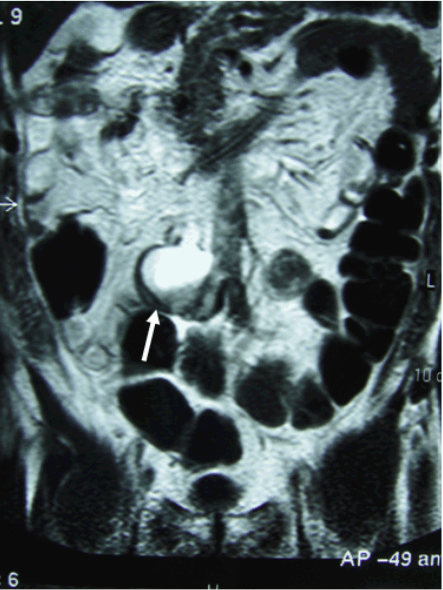

A long tube was inserted to reduce the symptoms of abdominal fullness and a small bowel series demonstrated a complete obstruction of the ileum (Figure 1). Magnetic resonance imaging (MRI) suggested a cystic lesion that might be correlated with the small bowel obstruction (Figure 2).

Figure 2: Magnetic resonance imaging. A 5 cm cystic lesion caused the small bowel obstruction.

Magnetic resonance imaging demonstrated a cystic lesion obstructing the ileum in the current patient, and a GI series showed the intestinal obstruction was far from the terminal ileum. These findings suggested that a cystic tumor in the small intestine or an appendiceal mucocele. While no definitive diagnosis could be made preoperatively and the latent possibility of cystadenocarcinoma could be also considered as a differential diagnosis.